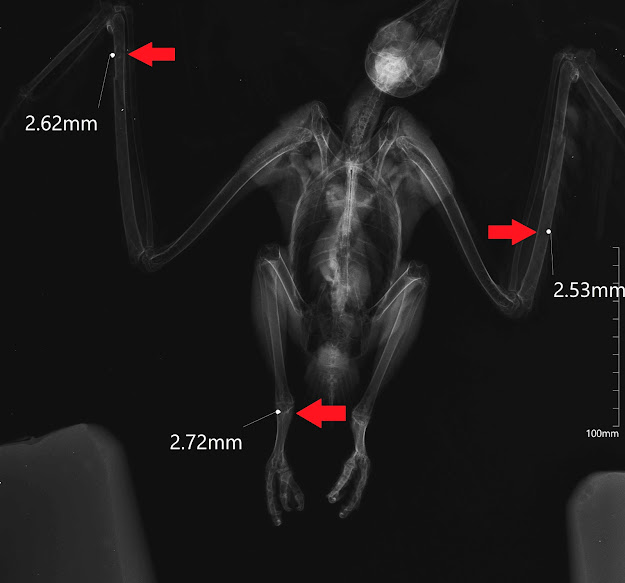

A terceira espécie, alvo da mesma crueldade, foi um milhafre-preto (Milvus migrans), uma ave de rapina que se alimenta principalmente de animais mortos, e que migra para Portugal em Março para nidificar.

Infelizmente, nem sempre é bem recebido por todos. Durante o exame físico, foram encontradas fraturas em ambos os cúbitos, correspondentes a dois dos três locais onde foi atingido por chumbo.

Foi então necessário fazer ligaduras nas asas, para evitar o movimento e consequente pioria da condição física, e administração de antibiótico. Apresentando também debilidade, por não se conseguir alimentar, recebeu fluídos sub-cutâneos para uma rápida hidratação, e foi-lhe fornecido alimento.

Foi então colocado numa das nossas câmaras de recuperação interiores para ser vigiado de perto nesta fase crítica.